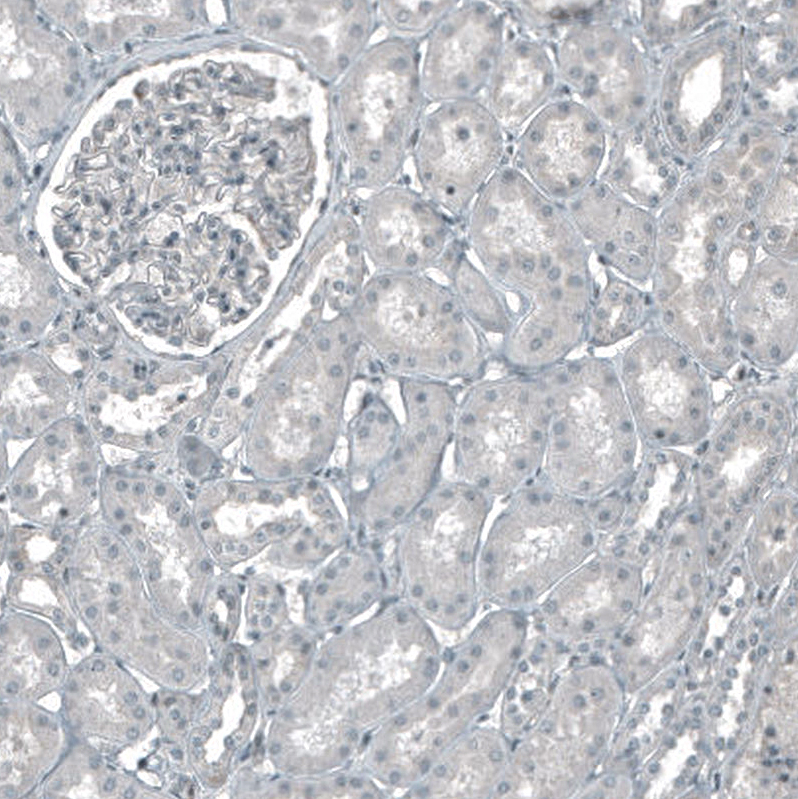

Immunohistochemistry analysis in human placenta and kidney tissues using AMAb91497 antibody. Corresponding CDK2 RNA-seq data are presented for the same tissues.